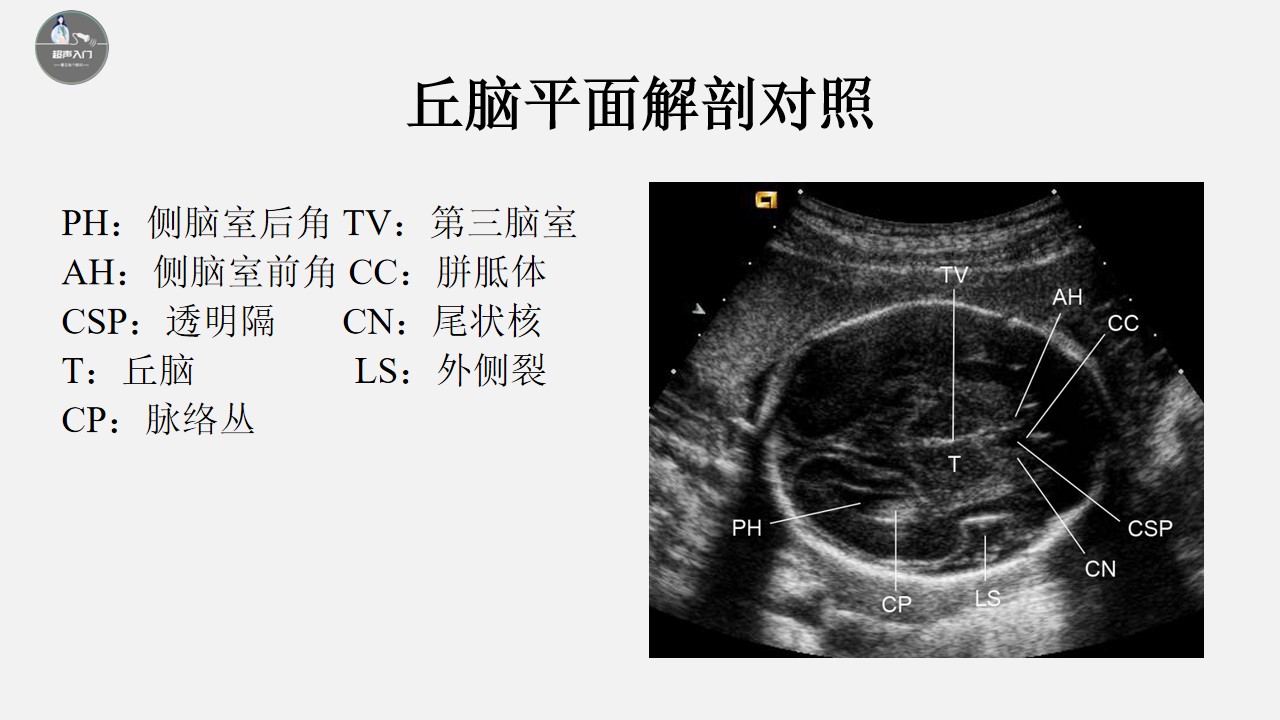

新生儿颅脑超声切面图 (新生儿颅脑超声诊断ppt)

胎儿颅脑超声标准切面图解,胎儿颅脑异常的超声诊断ppt